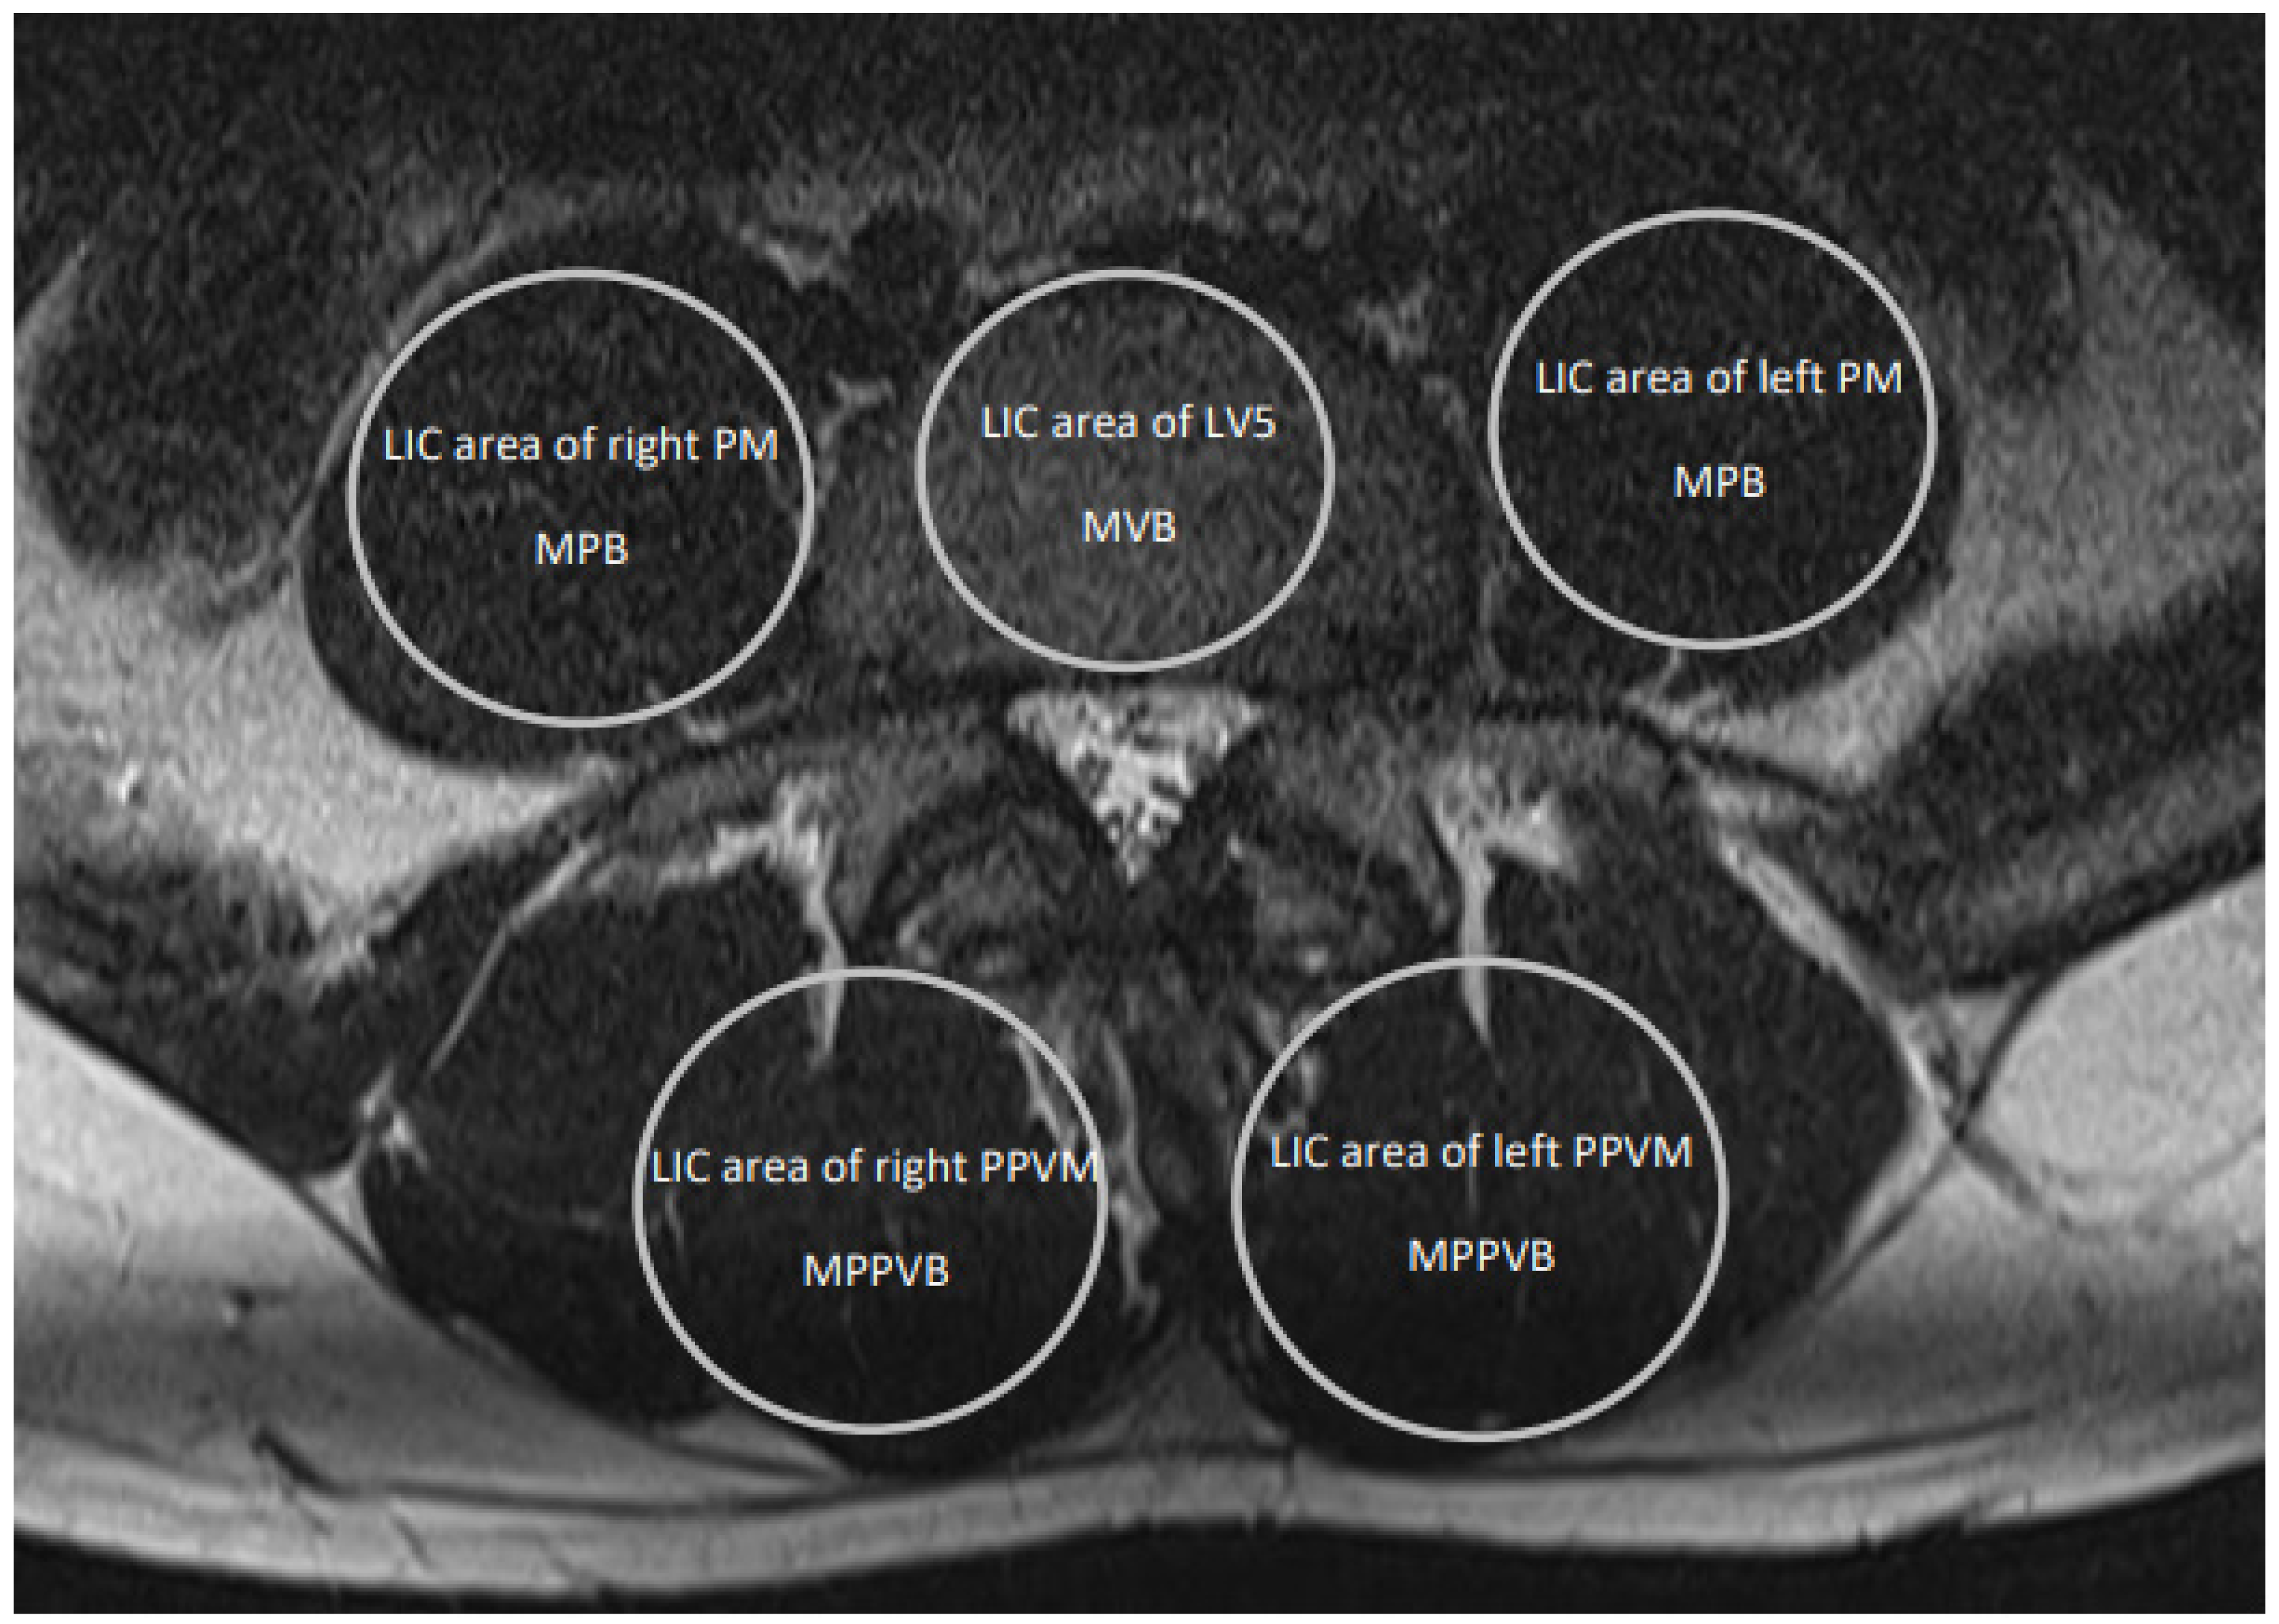

| LV5 LIC area size, mm2 | 801.4 (534.7–1103.6) | [759.6, 843.1] | 1004.4 (737.2–1279.9) | [967.0, 1041.7] | <0.001 | 1.6 |

| PM LIC area size, mm2 | 932.0 (489.6–1358.6) | [874.8, 989.1] | 1420.5 (485.3–1939.6) | [1329.7, 1511.3] | <0.001 | 2.0 |

| PPVM LIC area size, mm2 | 1035.9 (511.1–1670.0) | [941.9, 1129.9] | 1444.5 (628.0–2489.1) | [1322.6, 1566.4] | <0.001 | 1.2 |

| PM + PPVM LIC area size, mm2 | 1967.8 (1257.9–2926.7) | [1840.9, 2094.7] | 2865.0 (1848.9–4428.4) | [2681.8, 3048.3] | <0.001 | 1.8 |

| MVB | 174.5 (77.3–272.9) | [158.2, 190.8] | 160.0 (82.8–240.4) | [147.1, 172.8] | 0.17 | - |

| Normalized MVB | 0.43 (0.21–0.79) | [0.37, 0.48] | 0.35 (0.11–0.63) | [0.31, 0.39] | 0.02 | 0.6 |

| MPB | 73.7 (20.6–205.6) | [65.0, 82.4] | 66.3 (23.2–110.8) | [61.2, 71.4] | 0.15 | - |

| Normalized MPB | 0.18 (0.08–0.51) | [0.15, 0.21] | 0.14 (0.05–0.25) | [0.13, 0.16] | 0.03 | 0.6 |

| MPPVB | 141.9 (78.2–222.6) | [128.6, 155.1] | 114.1 (41.5–227.0) | [101.8, 126.4] | <0.001 | 0.7 |

| Normalized MPPVB | 0.33 (0.20–0.53) | [0.30, 0.36] | 0.23 (0.06–0.44) | [0.20, 0.25] | <0.001 | 1.2 |

| MTMB | 107.8 (20.6–222.6) | [97.0, 118.6] | 90.2 (23.2–227.0) | [81.8, 98.6] | 0.01 | 0.7 |

| Normalized MTMB | 0.26 (0.08–0.53) | [0.24, 0.29] | 0.19 (0.05–0.44) | [0.17, 0.20] | <0.001 | 0.7 |